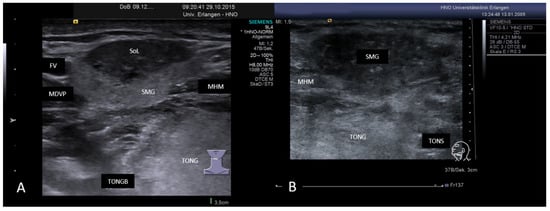

3.2. Findings in Normal Anatomy in Major Salivary Glands